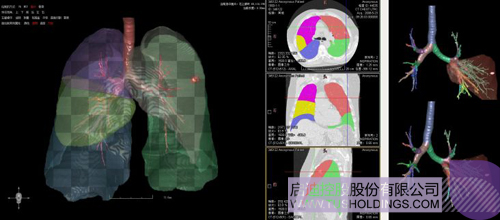

數字肺產品肺癌計算機輔助診斷

醫療影像智能分析是指運用人工智能技術、計算機視覺技術以及計算幾何技術對醫療影像進行自動分析,幫助醫生定位病癥、分析、跟蹤病情,并通過量化數據輔助醫生做出診斷,目前其旗艦產品“數字肺”已經覆蓋多種肺部疾病的早期檢測、診斷、跟蹤、術前規劃等完整的醫療流程。在臨床實踐中,超過80%的醫療數據來自醫療影像,這些影像數據通常需要專業醫生進行解讀,工作的重復性高、效率偏低。如果能夠運用智能影像分析技術,同時結合臨床表現以及既往病例進行全面分析,那么就可以大幅度提升影像診斷效率和準確性,讓專業醫生的寶貴時間集中在復雜病情的診斷和治療等環節。

數字肺——肺結節手術規劃系統